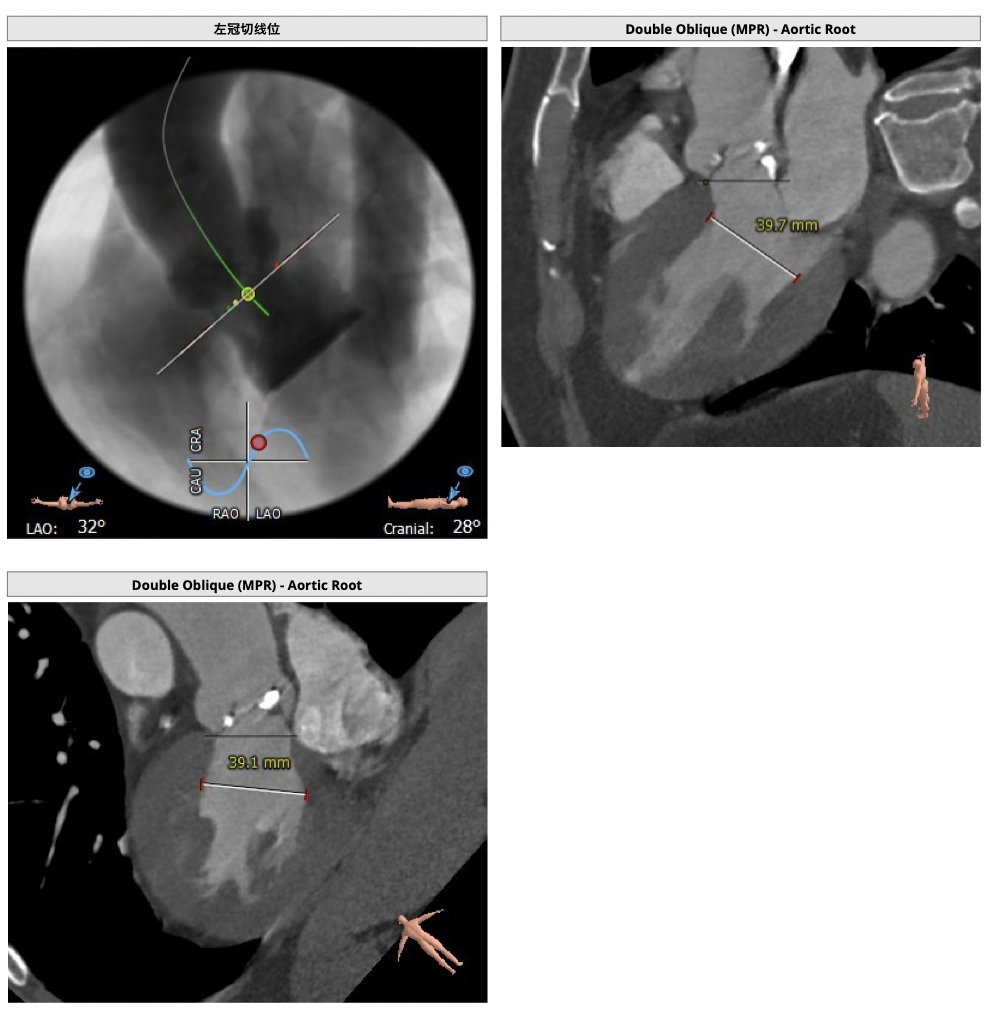

主动脉CT

图片

手术策略

难点分析:

*功能型二叶瓣,瓣叶增厚,重度钙化,瓣环及左室流出道层面仍可见钙化,左右可见钙化融合,瓣膜释放后发生瓣周漏的风险较高,瓣膜释放后容易移位。

*左右股动脉较细,直径小于6mm, 双侧髂动脉-股动脉走形迂曲,可见明显钙化,术中操作需谨慎轻柔,注意血管并发症的发生。

*左室腔较大,术中需注意液体管理。

制定策略:

经分析研判,拟从右侧股动脉穿刺入路,使用22mm球囊预扩,选用L26号的VenusA-Valve瓣膜,采用VenusA-Plus可回收输送系统进一步确保手术安全,瓣膜释放后结合造影和超声情况,决定是否后扩。